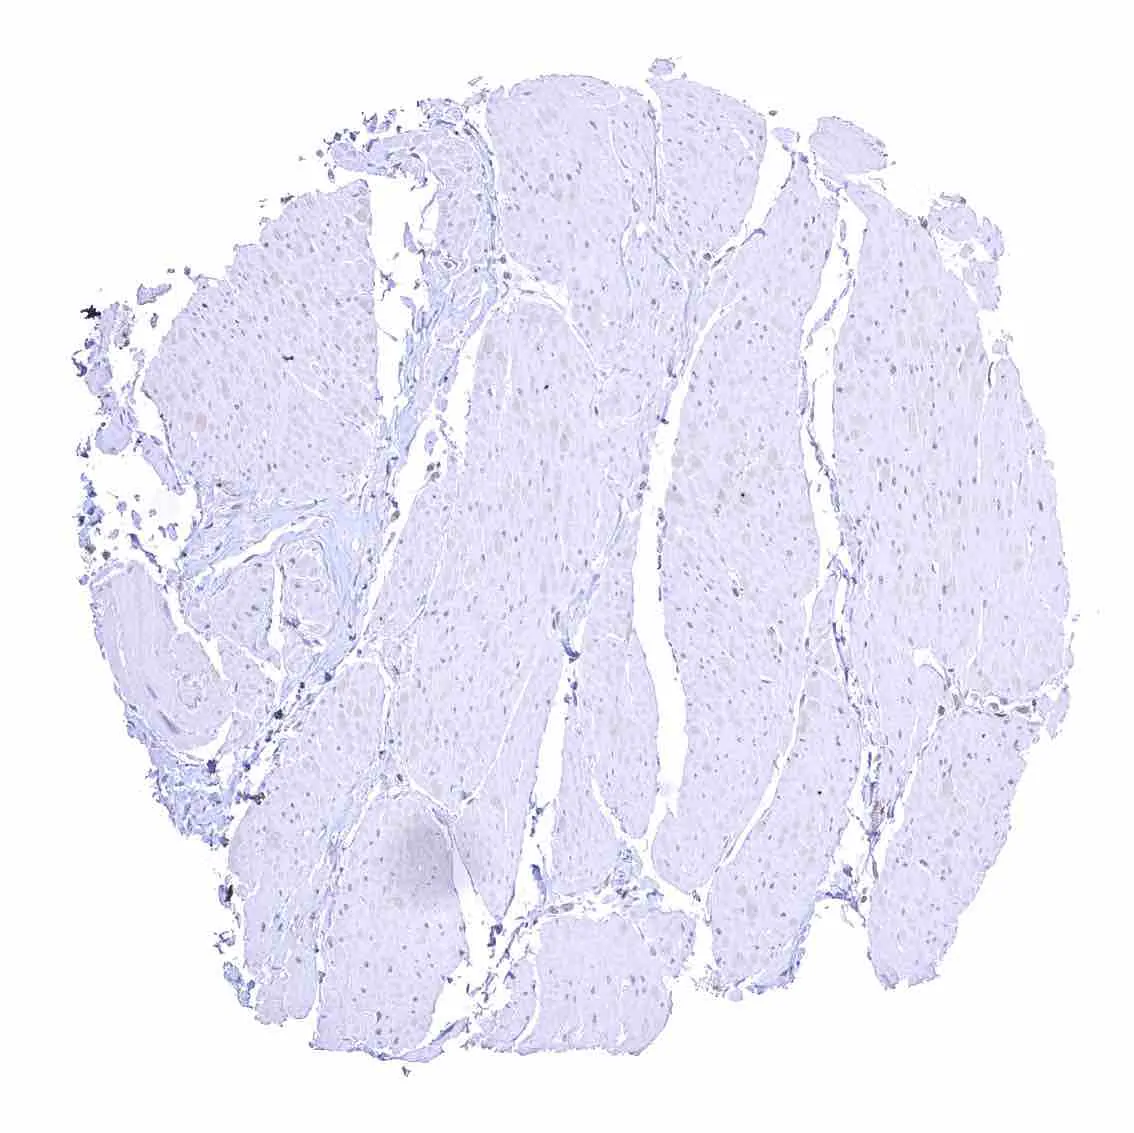

Skeletal muscle – Strong nuclear p27 staining of most but not all cells.